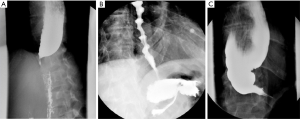

A standardized and validated symptom assessment such as the Eckardt score is useful in evaluation of patients. High resolution esophageal manometry testing should be used for the fine assessment of the esophageal motility, subtypes of the achalasia or characterization of other types of spastic esophageal disorders (Figure 1). The clinical significance of this sub-classification is a subject of debate. A contrast esophagram showing the classic “birds beak” appearance of the narrowed esophagogastric junction and esophageal aperistalsis should be evident (Figure 2A). Patients with spastic achalasia might have a “cork screw” appearance on the esophagogram (Figure 2B). In patients with late or end-stage achalasia, the esophagus may appear significantly dilated, angulated and tortuous alluding to a sigmoidal shape (megaesophagus) (Figure 2C). Megaesophagus has traditionally being approached surgically although it is not an absolute contraindication for POEM, however alternative therapies may be considered due to the increased technical difficulty (11-14). Identification of large amounts of residual food at the initial endoscopy would lead to aborting of POEM procedure to avoid mediastinal contamination (Figure 3).